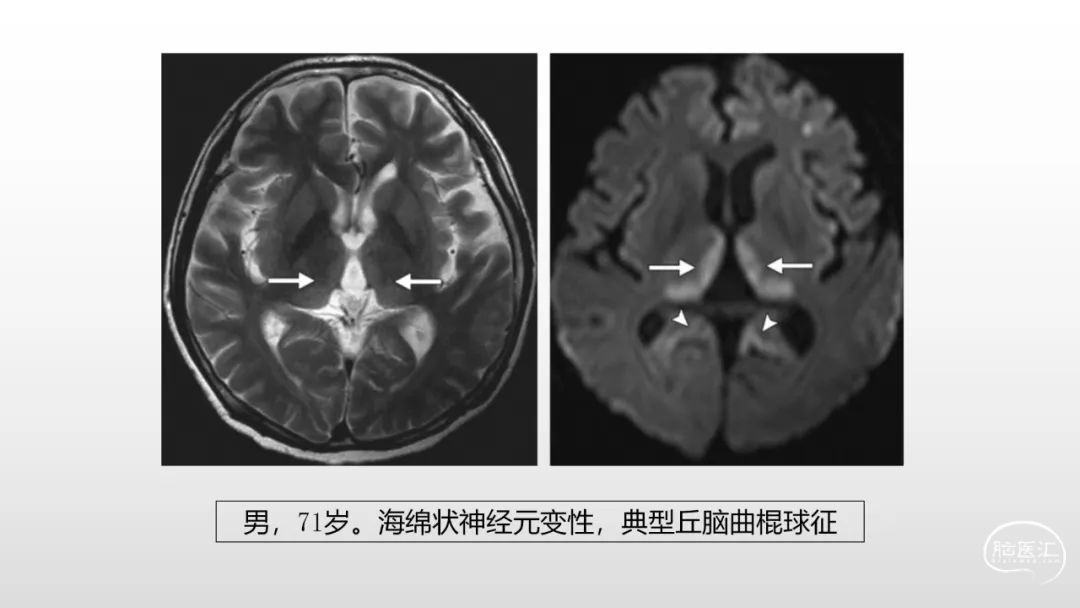

颅脑影像诊断基础知识讲座:感染和免疫性疾病2